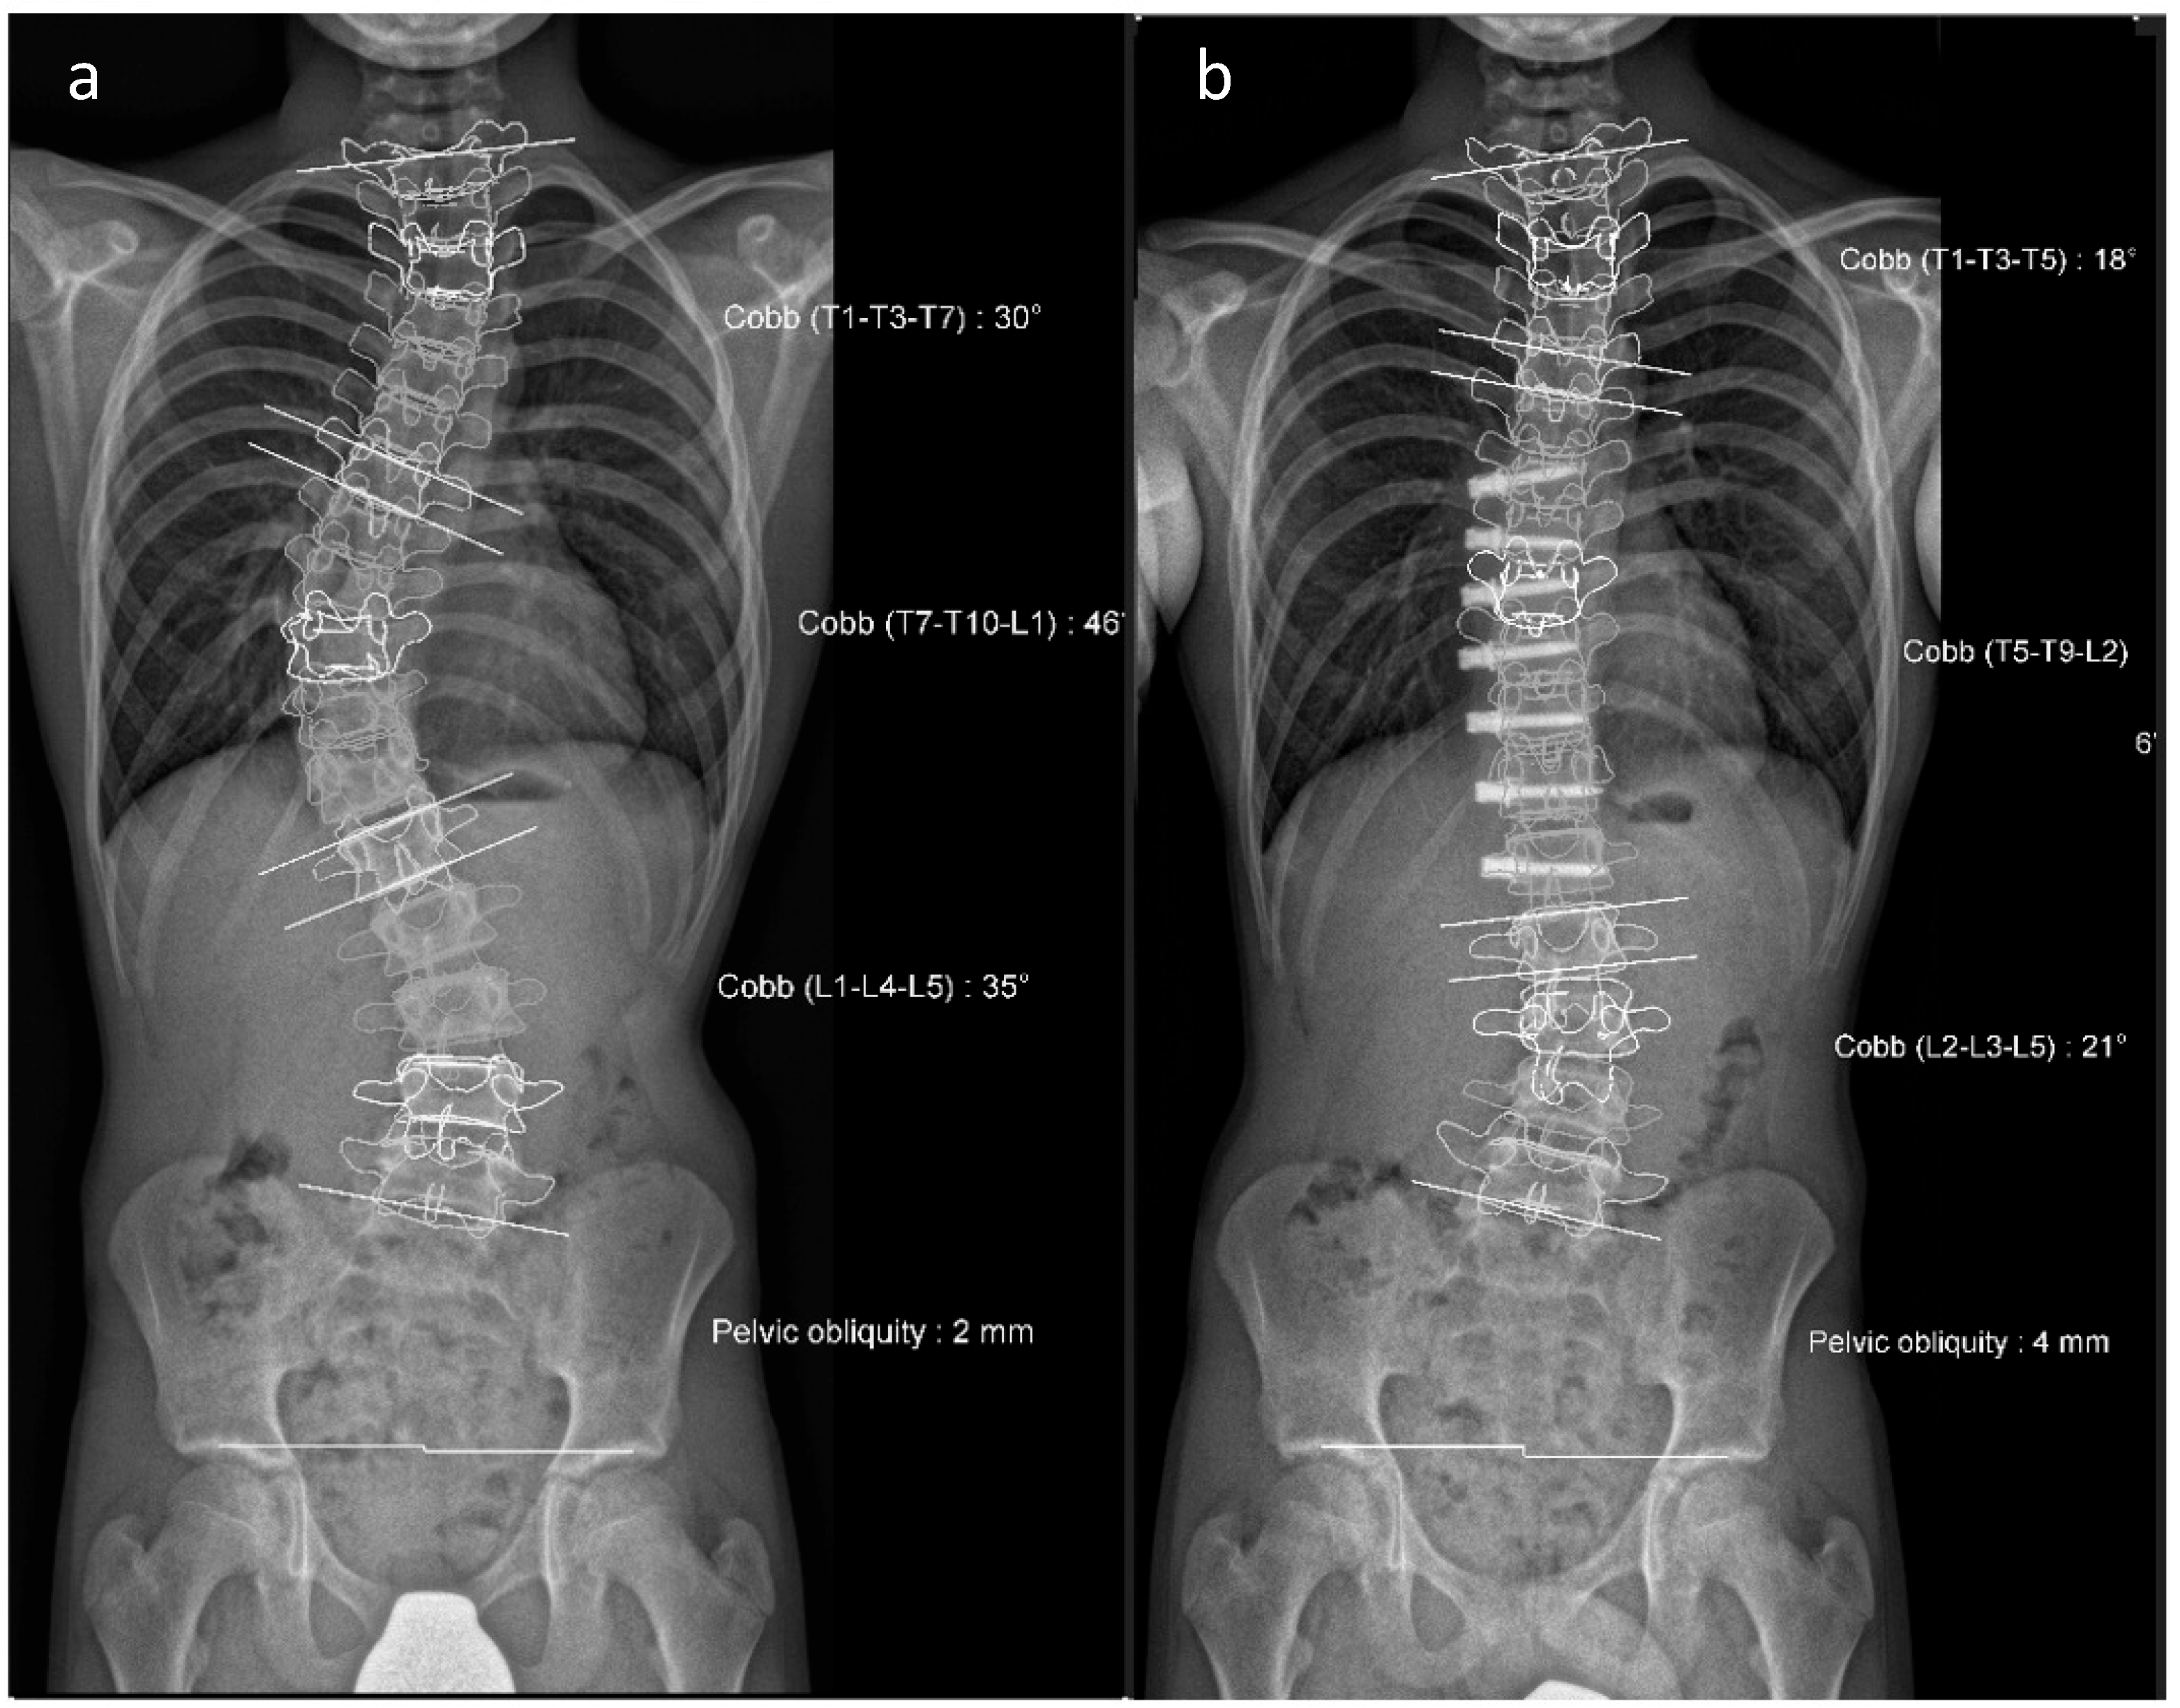

Figure 5. (a,b). Initial radiographs of a patient with adolescent idiopathic scoliosis. (c,d). Bending radiographs. (e,f). Postoperative image displaying implanted magnetically controlled growing rods as a dual rod system. (g,h). The patient was treated with a spondylodesis upon the completion of growth to maintain correction success (Reprinted with permission [10]).